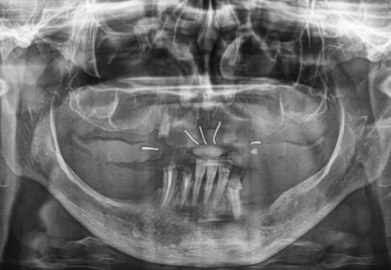

첫 방문 시 치과의사는 환자의 구강 상태를 평가하고, 임플란트가 적합한지 확인하기 위해 X-ray나 CT 촬영을 합니다. 이 과정은 일반적으로 한두 번의 방문으로 완료됩니다.